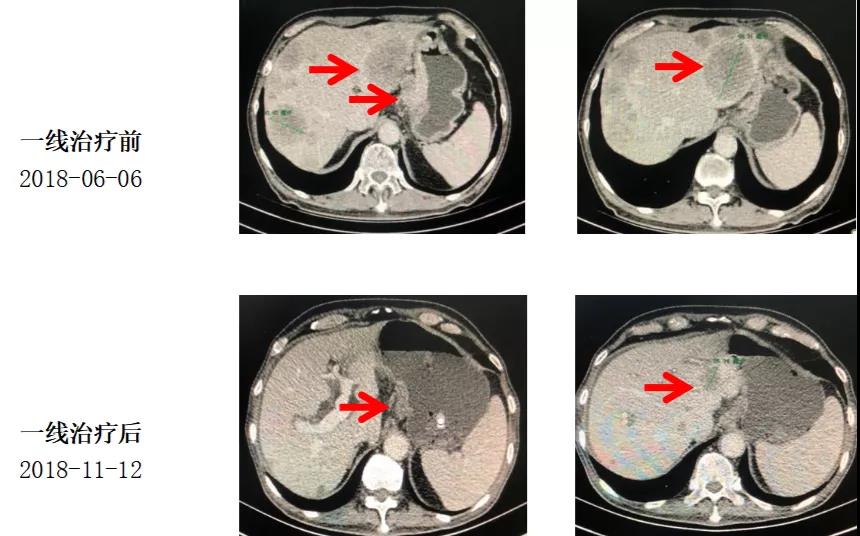

治疗经过:一线治疗

具体治疗方案:

替吉奥50mg bid,d1-14;力朴素 240mg d1;每3周重复

2018-06-16至2018-11-12,7程TS后疗效PR。综合考虑后建议转维持治疗。

治疗经过:维持治疗

具体治疗方案:

替吉奥 50mg bid D1-14每3周重复

2018-12-12至2019-06-04,肝多发转移灶,部分结节较前增大,CA199进行性(147.90U/ml-1275U/ml)升高,8周期替吉奥单药维持治疗后肿瘤PD。建议明确HER2状态,转二线治疗。